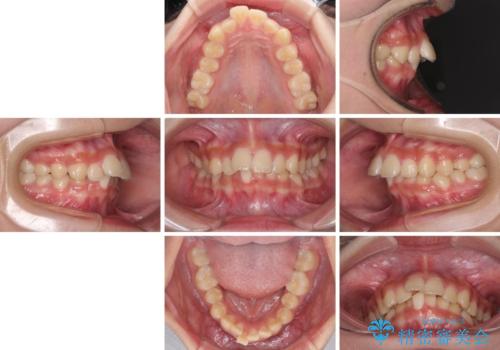

下の前歯が隠れてしまうほど深い咬み合わせ 高校生のインビザライン矯正治療

- 前歯の叢生と深い咬み合わせを気にして来院された患者様です。

奥歯の咬み合わせを見ると、上顎が下顎に対して相対的に前方にありました。

深い咬み合わせを改善するためには、上顎臼歯を後方に移動させつつ、下顎の小臼歯を直立させる必要があります。

インビザライン単体で対応ることも検討できますが、達成する可能性が低いため、カリエールディスタライザーという補助装置を併用して、より確実性を上げることとしました。

奥歯の咬み合わせと深い咬み合わせを改善した後、インビザラインで歯列を整えることとしました。